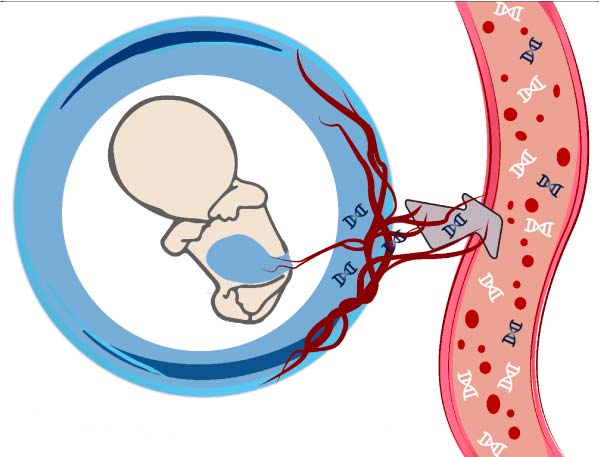

ADN FETAL EN SANGRE MATERNA

Se estudia lo siguiente:

– Cromosomas: 21 (Sd. de Down), 18 (Sd. de Edwards), 13 (Sd. de Patau), X (Sd. de Turner), Y (Sd. de Klinefelter).

– Deleción 22q11.2 / Síndrome

Di George.

– Triploidía / Vanishing twin / Embarazo Molar Completo.

– Sexo fetal.

– Embarazos generales.

A partir de las 10 semanas.

Se realiza en nuestro centro, obteniendo los resultados 10 días útiles después de tomada la muestra ya que ésta se envía a USA. No se necesita estar en ayunas.

ADN FETAL EN SANGRE MATERNA

Se estudia lo siguiente:

– CROMOSOMAS: 21 (Sd. de Down), 18 (Sd. de Edwards), 13 (Sd. de Patau), X (Sd. de Turner), Y (Sd. de Klinefelter).

– Deleción 22q11.2 / Síndrome

Di George.

– Triploidía / Vanishing twin / Embarazo Molar Completo.

– SEXO FETAL.

– EMBARAZOS GEMELARES.

– Adicionalmente se detectan las MICRODELECIONES en las regiones de:

1p36; 4p16.3; 5p15.2; 15q11.2 (Sd. de Angelman, Sd. de Prader-Willi, Sd. de Cri-du-chat).

A PARTIR DE LAS 10 SEMANAS.

Se realiza en nuestro centro, obteniendo los resultados 10 días útiles después de tomada la muestra ya que ésta se envía a USA.

No se necesita estar en ayunas.